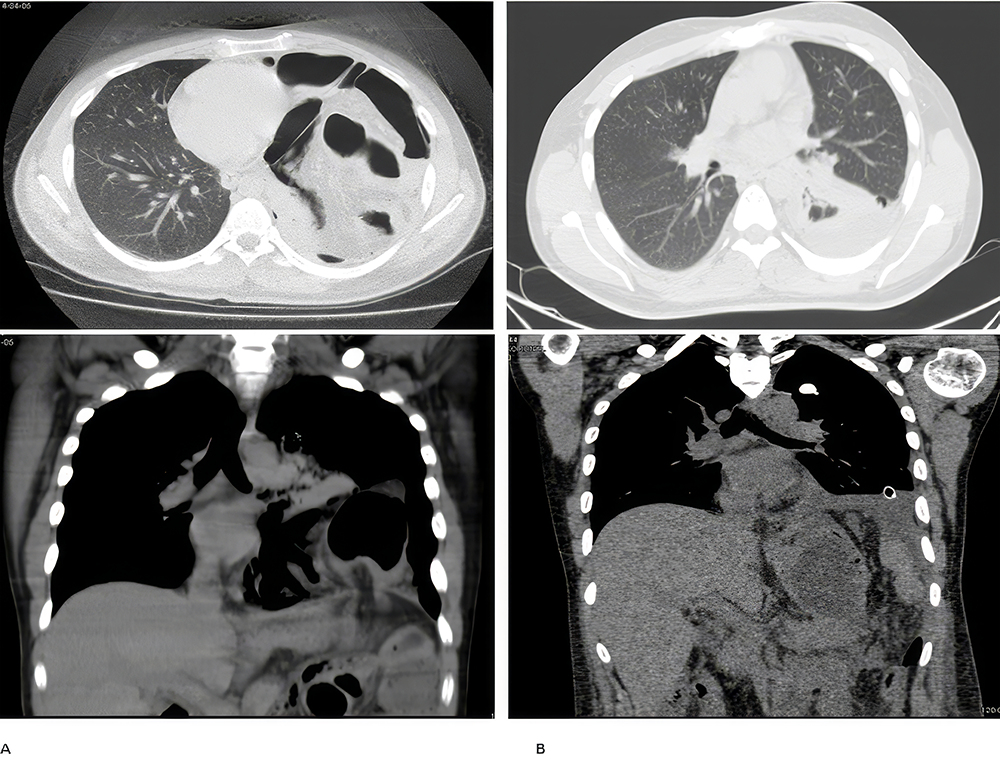

Among hernias requiring emergency intervention, 8 patients (42.1%) were operated on because of obstructive symptoms, while 6 (31.6%) others were operated on because of signs of strangulation (Figure 2). Organ perforation was present in 4 patients (21.1%) (stomach perforation in 2 patients and colon perforation in 2 patients). One patient (5.3%) was operated on for severe respiratory distress due to herniation of intraabdominal organs into the thorax from the defect caused by traumatic rupture of the diaphragm. One male infant diagnosed by contrast-enhanced tomography while being tested for respiratory distress in the second week after birth, was operated for sliding hernia of the stomach into the mediastinum and causing respiratory distress (Figure 3). General characteristics of the cases are presented in Table 1.

Figure 2. A: Strangulated colon within the diaphragmatic hernia secondary to a previous gunshot wound B: On postoperative day 5. Thorax tube and foreign body in the left lung, pleurisy, and partial atelectasis